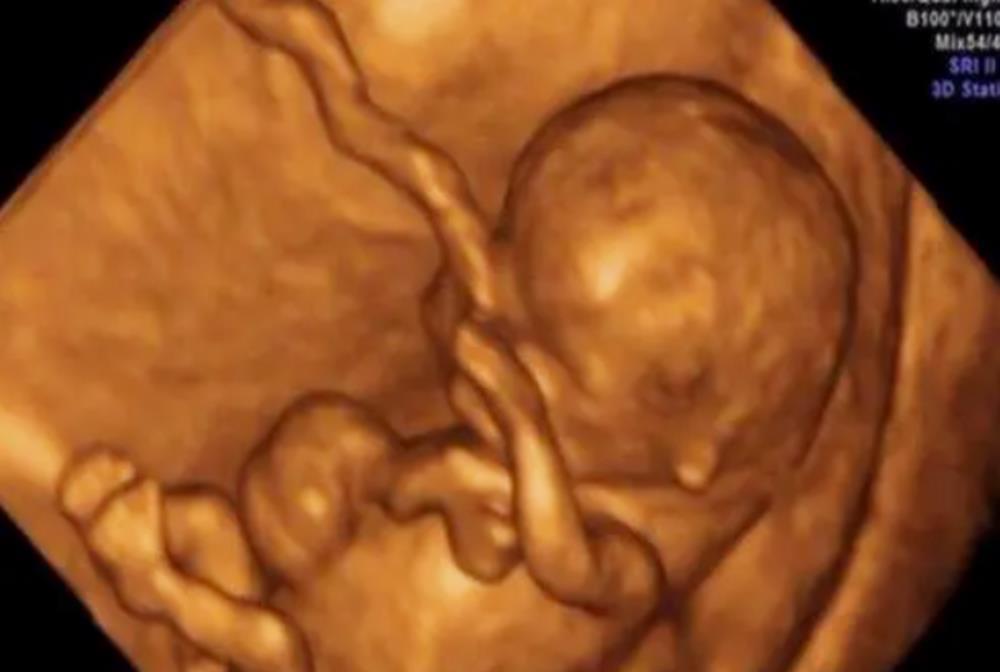

说到孕期检查,就不得不说做“大排畸”时做的四维彩超。

随着医学技术的发展,彩超检查也有了显著的提高,如今的四维彩超,不再是仅仅能感觉到宝宝的呼吸和运动,而是能亲眼目睹他们的一举一动和乖巧的笑容。

更重要的是,

四维彩超可以多方位、多角度地观察肚子里宝宝的生长发育情况

,能更好诊断出胎儿先天发育出现的畸形,所以说,在孕期每个妈妈都需要按照孕检项目做四维彩超。

三维彩超和四维彩超都是在同一个机器上完成,图像的分辨率和清晰度也都是一样的,唯一的区别就是前者是静态的,后者是动态的。

四维彩超如果能成像,孕妈还是要记得以视频的形式保留一份,因为这份图像可以说是宝宝第一张照片的留念。

另外,通过视频来看宝宝状态、轮廓、表情、动作等,会让父母真正看到了一个生命的表现和存在,而不是单纯地存在于妈妈的肚子里。